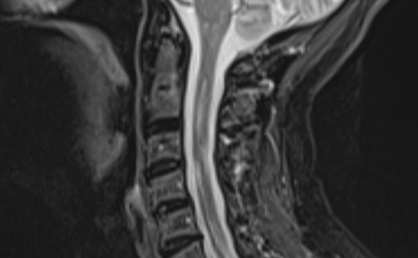

Black and white medical scan image of spine. Medical scan of cervical spine.

MS is caused by the immune system mistakenly attacking the nerves in the brain and spinal cord. Over time this can lead to the loss of nerves, which causes MS progression. Research in animals has shown that inflammation outside the brain can exacerbate this process, but researchers wanted to understand whether this happens in people with MS.

The study also builds on previous research which has found that infections can sometimes trigger a relapse or temporary worsening of symptoms in MS. This new study suggests that inflammation, which can be caused by infections like colds, flu and UTIs (urinary tract infections), is linked with the loss of nerve cells in the spinal cord – which is a major underlying cause of MS progression.

Over 150,000 people live with MS in the UK, with 135 diagnosed each week. The condition affects the brain and spinal cord, impacting how people move, think and feel. Symptoms are different for everyone, but can include fatigue, pain, vision problems and mobility issues. Most people are diagnosed in their 30s or 40s, but it can affect people of all ages, ethnic backgrounds and genders.